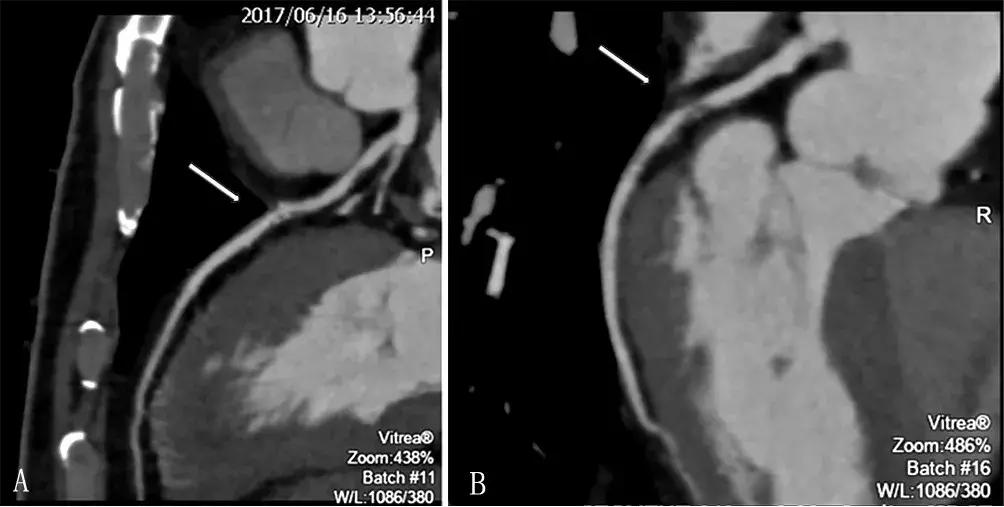

6月16日患者冠状动脉CT血管造影(CTA)检查结果:

(1)右冠状动脉中段非钙化斑块,管腔轻微狭窄(狭窄率为15%);

(2)左前降支近、中段钙化、非钙化斑块,管腔轻中度狭窄(狭窄率为30%~60%),左旋支近段钙化、非钙化斑块,管腔重度狭窄(狭窄率为80%),见图2。

图2 冠状动脉CTA检查结果

注:A为左前降支近、中段钙化、非钙化斑块,管腔狭窄为30%~60%(箭头指向处);B为左旋支近段钙化、非钙化斑块,管腔狭窄率为80%(箭头指向处)